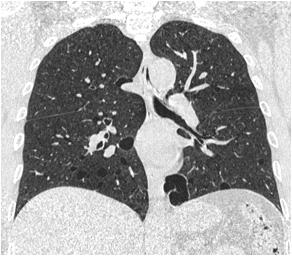

Majority of the patients had abnormal appearances of the HP region on MRI (Table 5) (Figs 1&2). Empty sella with varying thickness of the remaining pituitary tissue was the commonest abnormality noted (28 patients, 52.8% of the cohort). Only 3 patients (5.66%) had apparently normal looking HP region. Hypophysitis was diagnosed retrospectively in 1 lady with ES, whose previous MRI was consistent with hypophysitis11. One male with hypophysitis

Fig 2 — Upper panel: MRI of patients with craniopharyngioma. Mixed solid-cystic lesion with cystic component being hyperintense in both T1 (A) and T2 (B) weighted sequences

Lower panel: Patient with hypothalamic mass, that is isointense in T1 (C) with intense contrast enhancement (D)